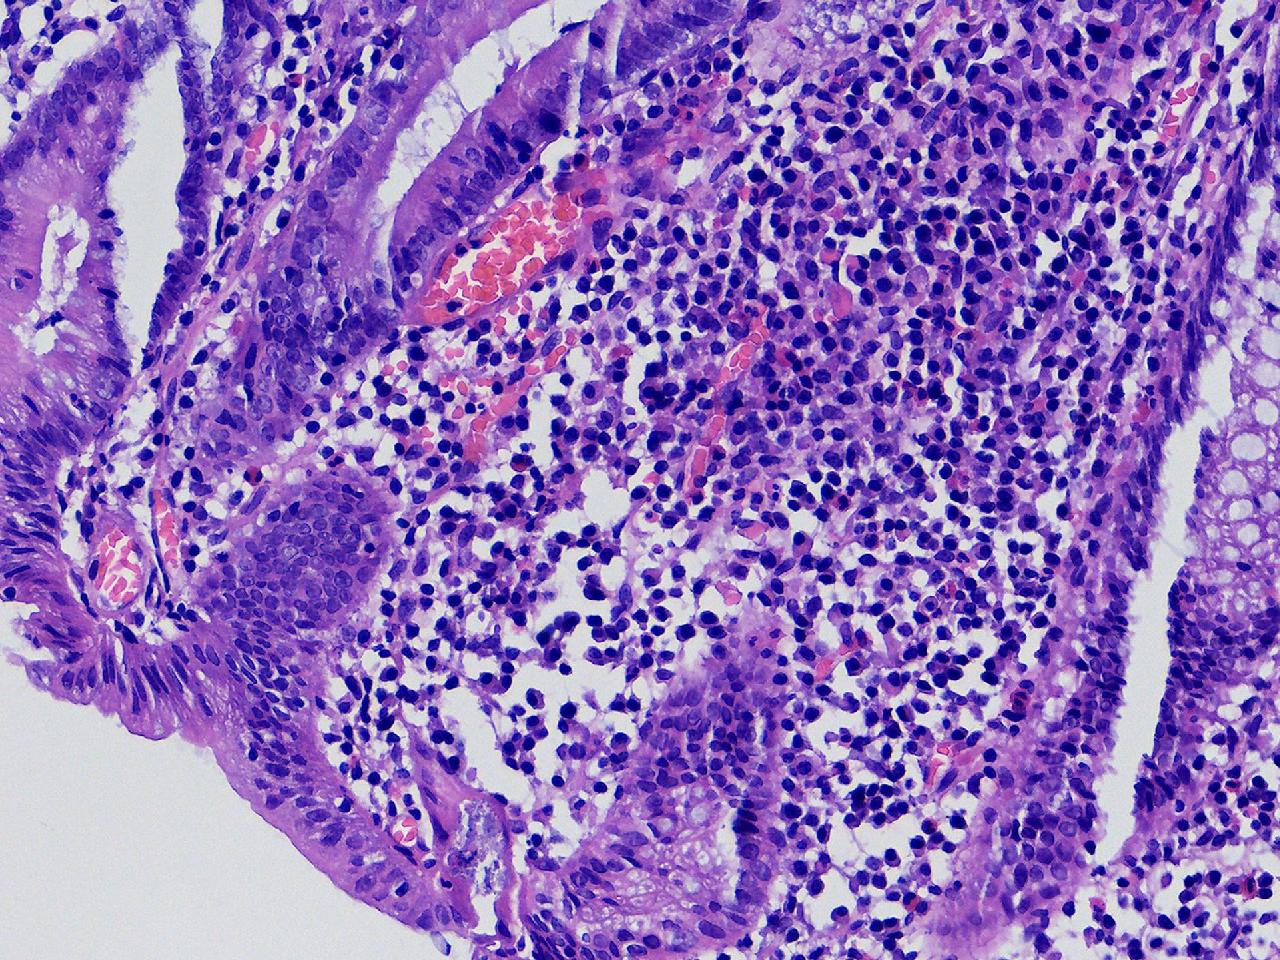

男,62岁,直肠见一直径约0.8cm大小的扁平隆起,表面光滑,活检1块。

直肠活检

灰白色不整形软组织1块,直径0.2厘米。

隐窝脓肿,杯状细胞减少,溃结考虑吗

炎症性肠病,溃结可能

不除外炎症性肠病,结合临床。